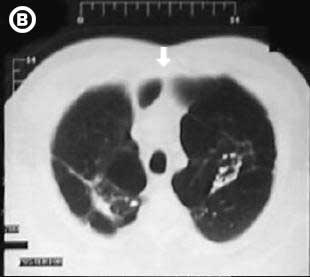

Corte Tomográfico

Corte tomográfico C, a nivel carina traqueal, observe el reforzamiento de la trama vascular e hilear pulmonar, el aspecto trabecular pulmonar y la gran bula pulmonar izquierda que ocupa el espacio retro esternal.

Corte tomográfico D, sub carinal, la redistribución del flujo pulmonar y el reforzamiento de la trama vascular hilear, gran bula retroesternal pulmonar izquierda